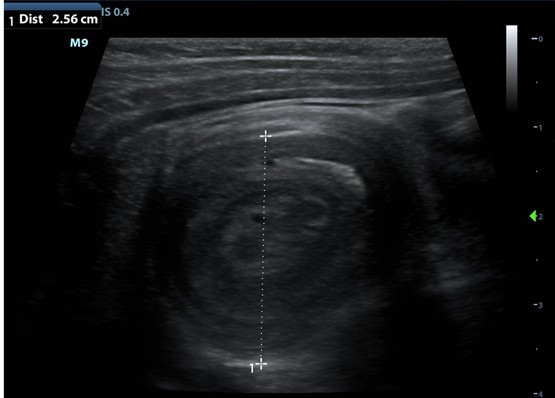

Patients do not need to be nothing by mouth (NPO) for diagnostic imaging. Abdominal ultrasonography is the first-line tool for diagnosis, as it is highly sensitive and specific. A complete examination includes evaluation of the entire abdomen in both longitudinal and transverse planes with a linear array transducer. In general, true ileocolic intussusception is positive when the classic target sign is over 2.5 cm in diameter and is found in the right side of the abdomen. It may include lymph nodes and mesenteric fat. Small bowel intussusceptions typically have a mean diameter of less than 2 cm.1,2 Occasionally, it can be difficult to differentiate between ileocolic and small bowel intussusceptions, as both may measure between 2 and 3 cm in size on ultrasound and as a doughnut-like lesion. In questionable cases, repeat ultrasonography after 20 minutes should be obtained to investigate whether the intussusception has resolved, as ileocolic intussusceptions are unlikely to self-resolve. Color duplex over the targetoid structure can suggest development of bowel ischemia if a lack of perfusion is seen. Computed tomography scan has been reported to be highly sensitive and specific in the diagnosis small bowel intussusceptions and can be helpful to identify pathologic lead points, but is time-consuming and exposes children to radiation.4,6

Figure-Ultrasound suggestive for ileocolic intussusception with a classic target sign, also termed “bull’s eye.”